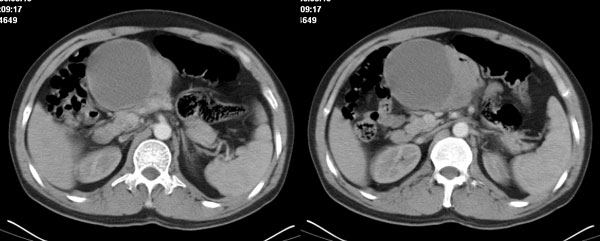

李**,男,46岁,便血1天入院,慢性贫血貌,腹平、软,剑突下压痛,肠鸣音稍活跃,hb大于1g/l,胃镜:慢性浅表性胃炎,b超:1肝内多发性占位 2腹腔内囊性肿块 ,肝内圆形影平扫ct值42.9,动脉期48.6,静脉期58.2,延迟期62.2

影像学表现:1 腹腔前中部、胰腺前方囊实性病灶(个人认为确定有否实性成分存在这是关键,涉及到鉴别诊断,如果是口服阳性造影剂则可明确左侧是不是小肠了),囊性部分囊壁不均,实性部分有强化,与小肠关系较密切,局部小肠受推移;与胰头、胃后壁均有脂肪间隙存在;2 胰腺无异常改变,胰周无渗出;3肝后段包膜下2个小圆形低密度灶,从图像和楼主提供的ct值来看有轻度强化,灶周无片状强化,不似单纯囊肿及肝癌、炎性病变表现;4 腹膜后及腹腔内无淋巴结肿大。

胰腺边界清晰,胰周筋膜不厚,胰周脂肪密度无明显增高;其前方囊实性病灶,边界清晰,增强后实性部分轻度强化;肝内多发边界清晰低密度影,增强后无明显强化(平扫ct值42.9,动脉期48.6,静脉期58.2,延迟期62.2)。